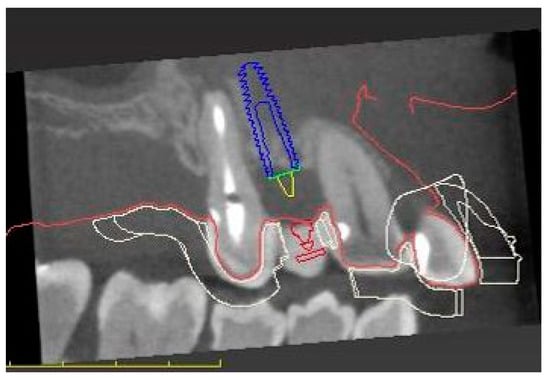

| Cone beam computed tomography scan | |

| Digital prosthetically driven implant planning | |

| Manufacturing of the surgical template | |

| Surgical | Computer-assisted implant surgery |